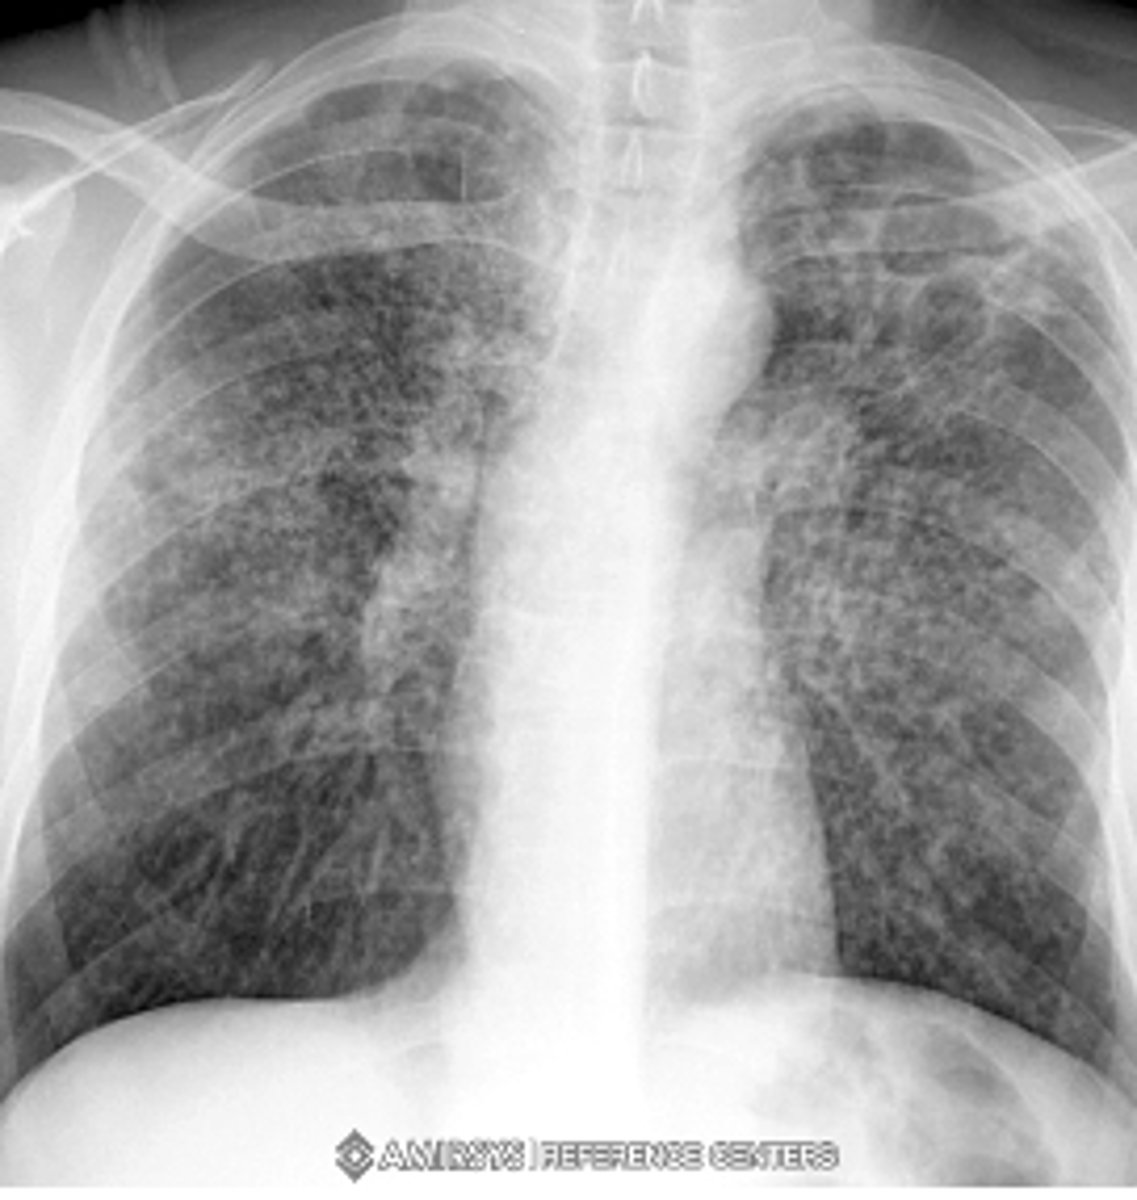

What is the pattern on the image of the back of the card?

Cystic PJP - PA chest radiograph shows diffuse bilateral reticulonodular interstitial infiltrates

<p>Cystic PJP - PA chest radiograph shows diffuse bilateral reticulonodular interstitial infiltrates</p>